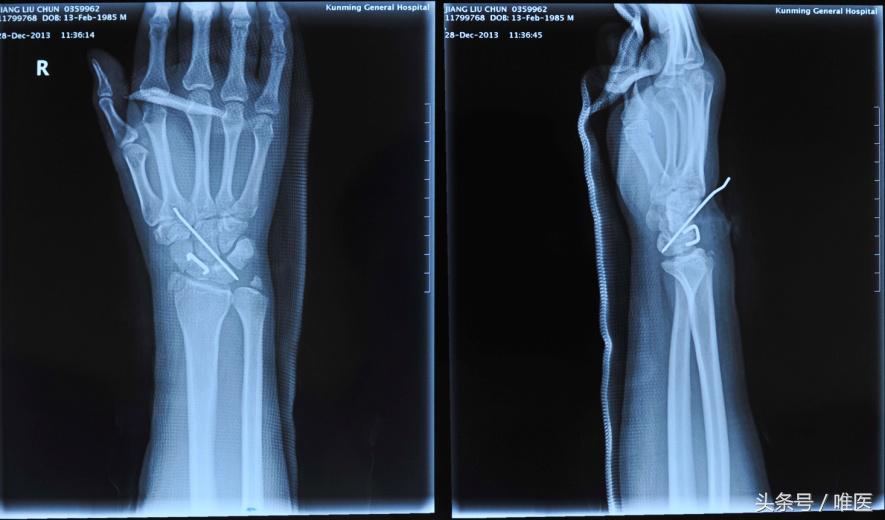

2.Herbert螺钉+辅助克氏针内固定

该术式是近年来许多临床医师尝试的一种新方法,并且取得了较好的成效,Hiren和Jeon等已较完善的阐明了可根据舟骨骨折的位置选择正确的术式,并且证实影像学监控下将螺钉置于中央区域、选择尽量长的螺钉、固定效果最佳,全螺纹螺钉生物效能最佳。临床上对于新鲜的经舟骨月骨周围脱位的患者应用此方法较为广泛,但Herbert螺钉固定方法学习曲线较长,对于临床经验和医疗设备上要求较高。